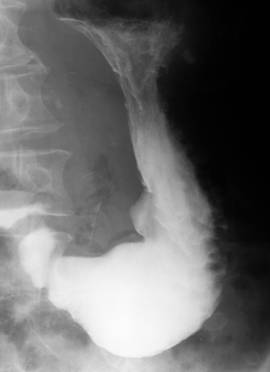

Aspects radiologiques des ulcere

sur la TOGD mono contrast est images directes en

epine , en doigtier ou image de Haudeck . Sur TOGD a double

de contrast on peu voyait aspect de face des ulceres sous

forme arrondie , ovalaire , en carte geographique

ou lineaire et tous sont accompagnement

d'un bourrelet peripherique oedemateux avec la

convergence des plies muqueuse saint

vers lequel .

Image en epine d'une ulcere

de la portion verticale du petit courbure |

Aspect en doigtier d'une

ulcere de la petit courbure |

Ulcer du portion verticale de la petit

coubure de l'estoma |